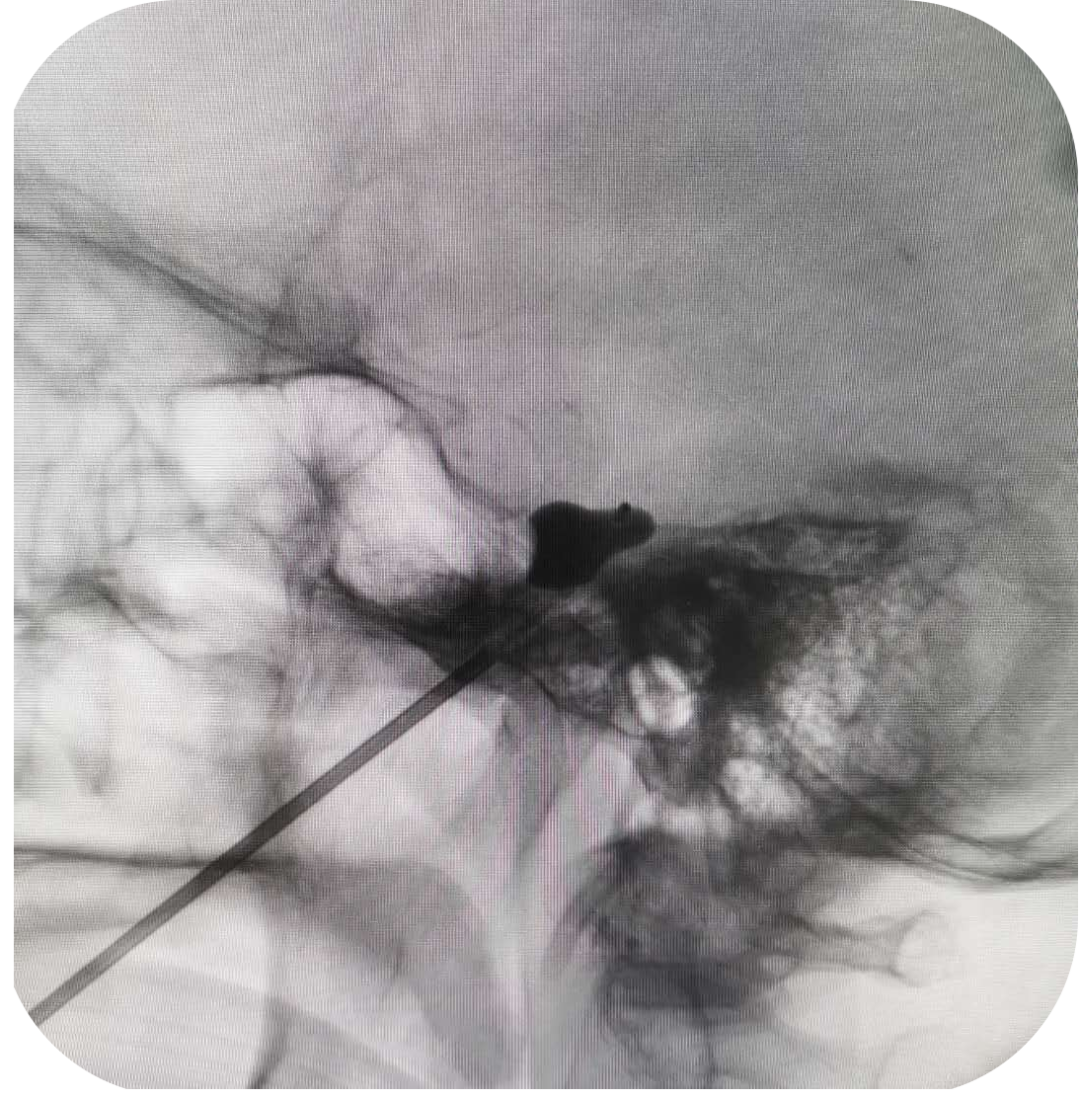

在患者入睡后,在C型臂定位引导下,精确将穿刺针送到颅底的卵圆孔内

e2c31d51910f352c759221ff4415d82a.jpg

再将微导管送进三叉神经节所在的美克氏腔

用1ml注射器将造影剂注入微球囊内,对半月神经节压迫数分钟